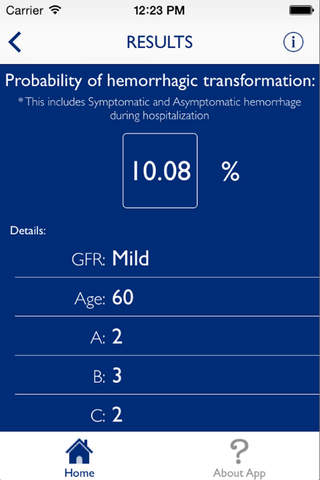

The HeRS (Hemorrhage Risk Stratification) calculator is an application that aids in determining the probability of hemorrhagic transformation of acute ischemic stroke in patients with an indication for anticoagulation. It is a prospectively validated score.

The HeRS score is a prospectively validated equation based on continuous variables of age, renal function, and stroke size. The equation is complex and cannot be performed easily or quickly with paper or with an ordinary calculator. Determining the probability of hemorrhagic transformation of acute ischemic stroke is clinically useful as risk of hemorrhage often needs to be weighed against risk of recurrent stroke in deciding on whether or not to anticoagulate in the acute clinical setting. The HeRS score provides one of these valuable pieces of data- the likelihood of hemorrhagic transformation. Using the mobile application, the HeRS score can be accurately and easily determined rapidly.

The HeRS score is a prospectively validated equation based on continuous variables of age, renal function, and stroke size. The equation is complex and cannot be performed easily or quickly with paper or with an ordinary calculator. Determining the probability of hemorrhagic transformation of acute ischemic stroke is clinically useful as risk of hemorrhage often needs to be weighed against risk of recurrent stroke in deciding on whether or not to anticoagulate in the acute clinical setting. The HeRS score provides one of these valuable pieces of data- the likelihood of hemorrhagic transformation. Using the mobile application, the HeRS score can be accurately and easily determined rapidly.